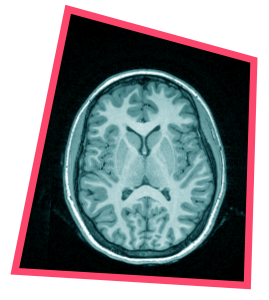

“The brain I find truly magical. It’s a bit like the universe. On the one hand very ordinary, everyone has one, and on the other hand very complex and unfathomable. How all the neurons work together is something we still understand very little about.”

“During my studies in Pittsburgh I learned how to map brain activity with fMRI while someone performs a task. Back in the Netherlands I set up a lab to investigate how young people’s risk behaviour is related to emotions. In adults it was already known that emotion centres play a role, and I wanted to see how those rational and emotional brain regions work together in the adolescent brain. In 2005 I started my first experiments. Through lectures in which I talked about my book The adolescent brain, so many enthusiastic parents and young people signed up that I had more participants than I could include.

“Using fMRI we looked at what happens in the brain as the risk in the gambling game increased and the person was right or wrong. We studied various emotion centres, with a leading role for the ventral striatum. That is an emotion centre that responds to stimuli from risky behaviour. Those brain regions are often seen as the main reason young people start vaping, drinking alcohol or breaking the rules.”